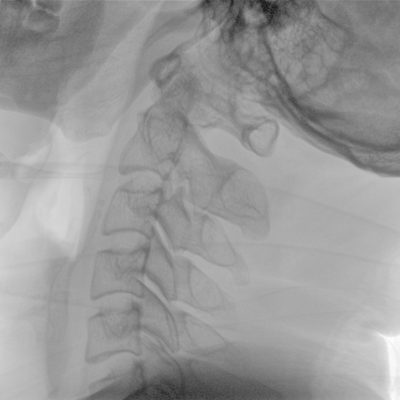

骨科: 經(jīng)皮錐體成形術(shù)、經(jīng)皮椎間盤臭氧治療術(shù)、胸脊椎固定、骨活檢、腰椎內(nèi)固定術(shù)等。

優(yōu)質(zhì)平板探測(cè)器、可靈活升降調(diào)節(jié)SID、獨(dú)特圖像處理系統(tǒng)、高品質(zhì)濾線柵,大視野成像清晰不失真。